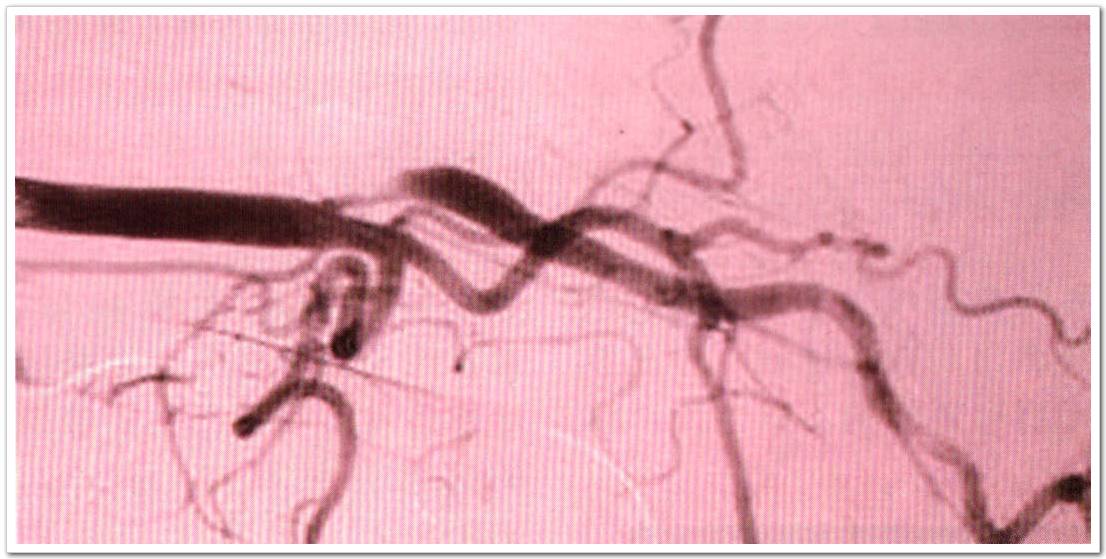

血管性血友病因子抗原(von Wi11ebrand factor antigen,VWF:Ag)是由內(nèi)皮細(xì)胞和巨核細(xì)胞合成的粘附性的血漿糖蛋白多聚體,血管性血友病因子前肽(von Willebrandfactor propepticle,VWF:AgII)是由VWF分解為VWF:Ag和VWF:Ag II。內(nèi)皮細(xì)胞分泌VWF,將其排放到血液或者內(nèi)皮下基質(zhì),或者儲(chǔ)存在VWFWeibel Palade小體內(nèi)。在急性內(nèi)皮細(xì)胞激活系統(tǒng)中,VWF:AgII比VWF:Ag可能是更敏感的指標(biāo)。因?yàn)閂WF:Ag II有較短的血漿半衰期,并且可迅速返回基線濃度,刺激內(nèi)皮細(xì)胞活性后消除。在無癥狀與有癥狀頸動(dòng)脈狹窄患者中,這些標(biāo)志物并沒有同時(shí)評(píng)估過。經(jīng)顱彩色多普勒超聲(transcranial Doppler ultrasound,TCD)檢測(cè)的微栓子信號(hào)(microembolic singals,MES)與內(nèi)皮細(xì)胞的活化之間的關(guān)系還不清楚。

來自愛爾蘭國家兒童中心神經(jīng)內(nèi)科的McCabe等人在此多中心觀察性研究中,受試者為頸動(dòng)脈狹窄≥50%的患者,受試者被分為無癥狀組(31例),early phase癥狀組(46例,缺血性卒中或TIA發(fā)作后4周之內(nèi))和late phase癥狀組(35例,缺恤性卒中或TIA發(fā)作后3個(gè)月以上),在late phase癥狀組中,23例患者已經(jīng)接收了頸動(dòng)脈介入手術(shù),稱為late phase介入組。對(duì)比無癥狀組、early phase癥狀組、late phase癥狀組患者的VWF:Ag及VWF:Ag II水平。對(duì)有癥狀的患者進(jìn)行隨訪評(píng)估。TCD監(jiān)測(cè)將患者分為MES陽性組或陰性組。

實(shí)驗(yàn)結(jié)果表明:VWF:Ag II水平,early phase癥狀組患者(12.81g/ml;P<0.001)、late phase癥狀組患者(10.61g/ml;P=0.01)和late phase介人組患者(10.61g/ml;P=0.038) 與無癥狀組相比較(8.9g/ml)均明顯增高。VWF:Ag水平,在有癥狀患者隨訪期間,從發(fā)病早期到晚期逐漸下降(P=0.048)。early phase癥狀組而且MES陰性的患者比無癥狀組而且MES陰性的患者VWF:Ag II水平增高(13.3vs9.0lg/ml;P<0001)。

此研究結(jié)論:癥狀性頸動(dòng)脈狹窄患者與無癥狀性頸動(dòng)脈狹窄患者相比,內(nèi)皮細(xì)胞活性增強(qiáng);early phase癥狀組而且MES陰性患者與無癥狀的MES陰性患者相比內(nèi)皮細(xì)胞活性增強(qiáng);而在有癥狀的患者中內(nèi)皮細(xì)胞活性隨著時(shí)間延長(zhǎng)而而下降。在頸動(dòng)脈狹窄患者中,VWF:Ag II水平比VWF:Ag更敏感。MES檢測(cè)結(jié)合腦血管內(nèi)皮標(biāo)志物在預(yù)測(cè)頸動(dòng)脈狹窄卒中風(fēng)險(xiǎn)中的潛在價(jià)值值得進(jìn)一步研究。